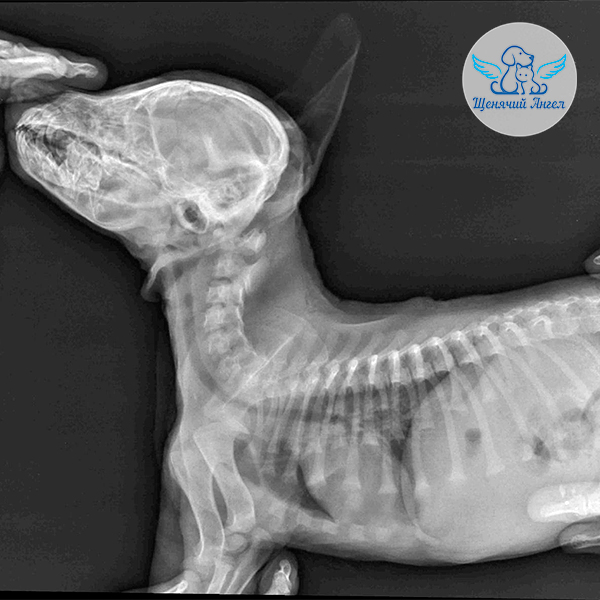

Был проведён рентген 🩻 . В области теменной части головы отмечаются рентгенопрозрачные линии – предположительно это швы костей черепа, однако полностью исключить перелом по ним нельзя. Позвоночник и органы грудной клетки – без видимых патологий.